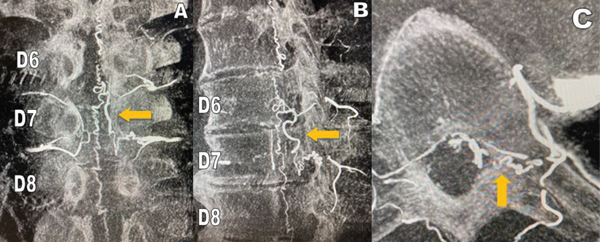

Por los antecedentes anteriormente mencionados y con el requerimiento de un centro de mayor complejidad, se decide la derivación a nuestra institución para su estudio. Al interrogatorio el paciente relata dolor lumbar y ciatalgia bilateral de más de 18 meses de evolución, con dificultades en la marcha, que progresaron hasta necesitar asistencia en silla de ruedas, agregando afectación esfinteriana en el último tiempo. Al examen físico, presentó paraparesia flácida severa, hiporreflexia tendinosa y nivel sensitivo desde T10. Se interpretó en un primer momento, por imágenes previas, como Mielomalacia en estudio. Por la evolución del cuadro clínico, se realizó en primera instancia una RMN dorsal con contraste endovenoso donde se observó realce vascular intracanal a nivel de D7 en secuencia T1 y un vaso serpinginoso en secuencia STIR (Figura 2). Se completó el estudio con Angiografía Vertebromedular donde se observó fístula arteriovenosa dural espinal (FAVd), que se origina a nivel de D7 izquierda, con gran congestión venosa a lo largo del canal (Figura 3). La Arteria Radicular Magna de Adamckievicz se localizó en L1 derecha. Se decidió realizar tratamiento quirúrgico por ser paciente con bajas comorbilidades, presencia de FAVd a nivel dorsal y reportes de alta tasa de éxito de la patología por microcirugía. Se realizó hemilaminectomia izquierda a nivel D7, localización de trayecto fistuloso a nivel foraminal, colocación de clip transitorio, coagulación con pinza bipolar y resección de fístula con microtijera (Figura 4). El paciente evolucionó con peoría de su patología renal de base e infección del tracto urinario lo que imposibilitó su control por imágenes posoperatorios.

Figura 2: RMN columna dorsal con contraste que muestra vaso serpinginoso a nivel D7 (flecha): A) Estudio en secuencia T1. B) Estudio en secuencia STIR.

Figura 3: Angiografía vertebromedular en 3 vistas sucesivas que demuestran el origen y el trayecto recorrido por la FAVd originado a nivel del foramen izquierdo de D7 (flecha naranja): A) corte frontal, B) corte sagital, C) corte axial.